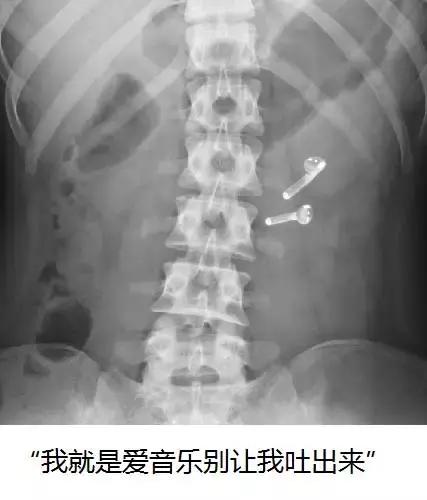

4.吞食异物

这也是比较常见的便血诱因之一。很多狗狗会出于好奇误食瓶盖、鱼线、玩具等异物,也有一些主人喜欢在自己做饭的时候喂狗狗几块骨头。这些东西很可能在消化过程中划伤狗狗的肠道黏膜,从而引发溃疡和便血。有些时候异物还会堵塞肠道,甚至诱发肠套叠,这个时候就只有手术才能解决了。